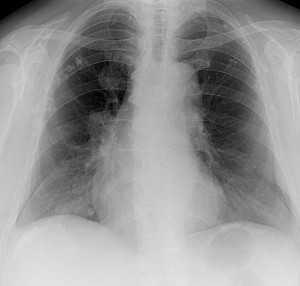

Метастазы в легких — фото рентгенограммы. Округлые тени — метастазы рака пищевода. Хорошо виден большой узел округлой формы вблизи переднего отрезка 2-го ребра. На снимке справа - циркулярное сужение пищевода за счет опухолевого утолщения его слизистой оболочки.